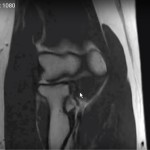

- MRI: best study to diagnose complete tear of the MCL of the elbow